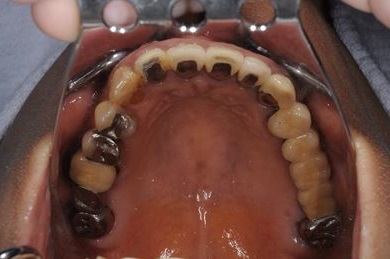

インプラントの症例写真 IMPLANT

抜歯即日スピードインプラント治療

| 性別/年齢 | 女性 / 44歳 | ||||||||||||||||||||||||||||||||

| 主訴 | 上のさし歯がグラグラする。インプラントにした方が良いのか、相談したい。 | ||||||||||||||||||||||||||||||||

| 治療方針 | 抜歯と同時にインプラントを埋入し、治療期間を短縮する。 | ||||||||||||||||||||||||||||||||

| 治療内容 | インプラント2本(抜歯即日スピードインプラント)、メタルボンドセラミック2本 | ||||||||||||||||||||||||||||||||

| 総治療費 | 458,588円 | ||||||||||||||||||||||||||||||||

| 治療期間 | 6ヶ月 |